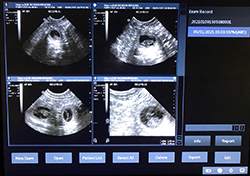

Mobile Ultrasound Pregnancy Scanning and Microchipping Services

Puppy Love scan and chip